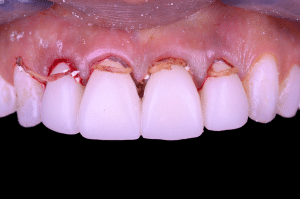

Fig 3

Les couronnes transitoires sont ainsi scellées à l’aide de Temp-Bond de Kerr, que l’on laisse complètement durcir.